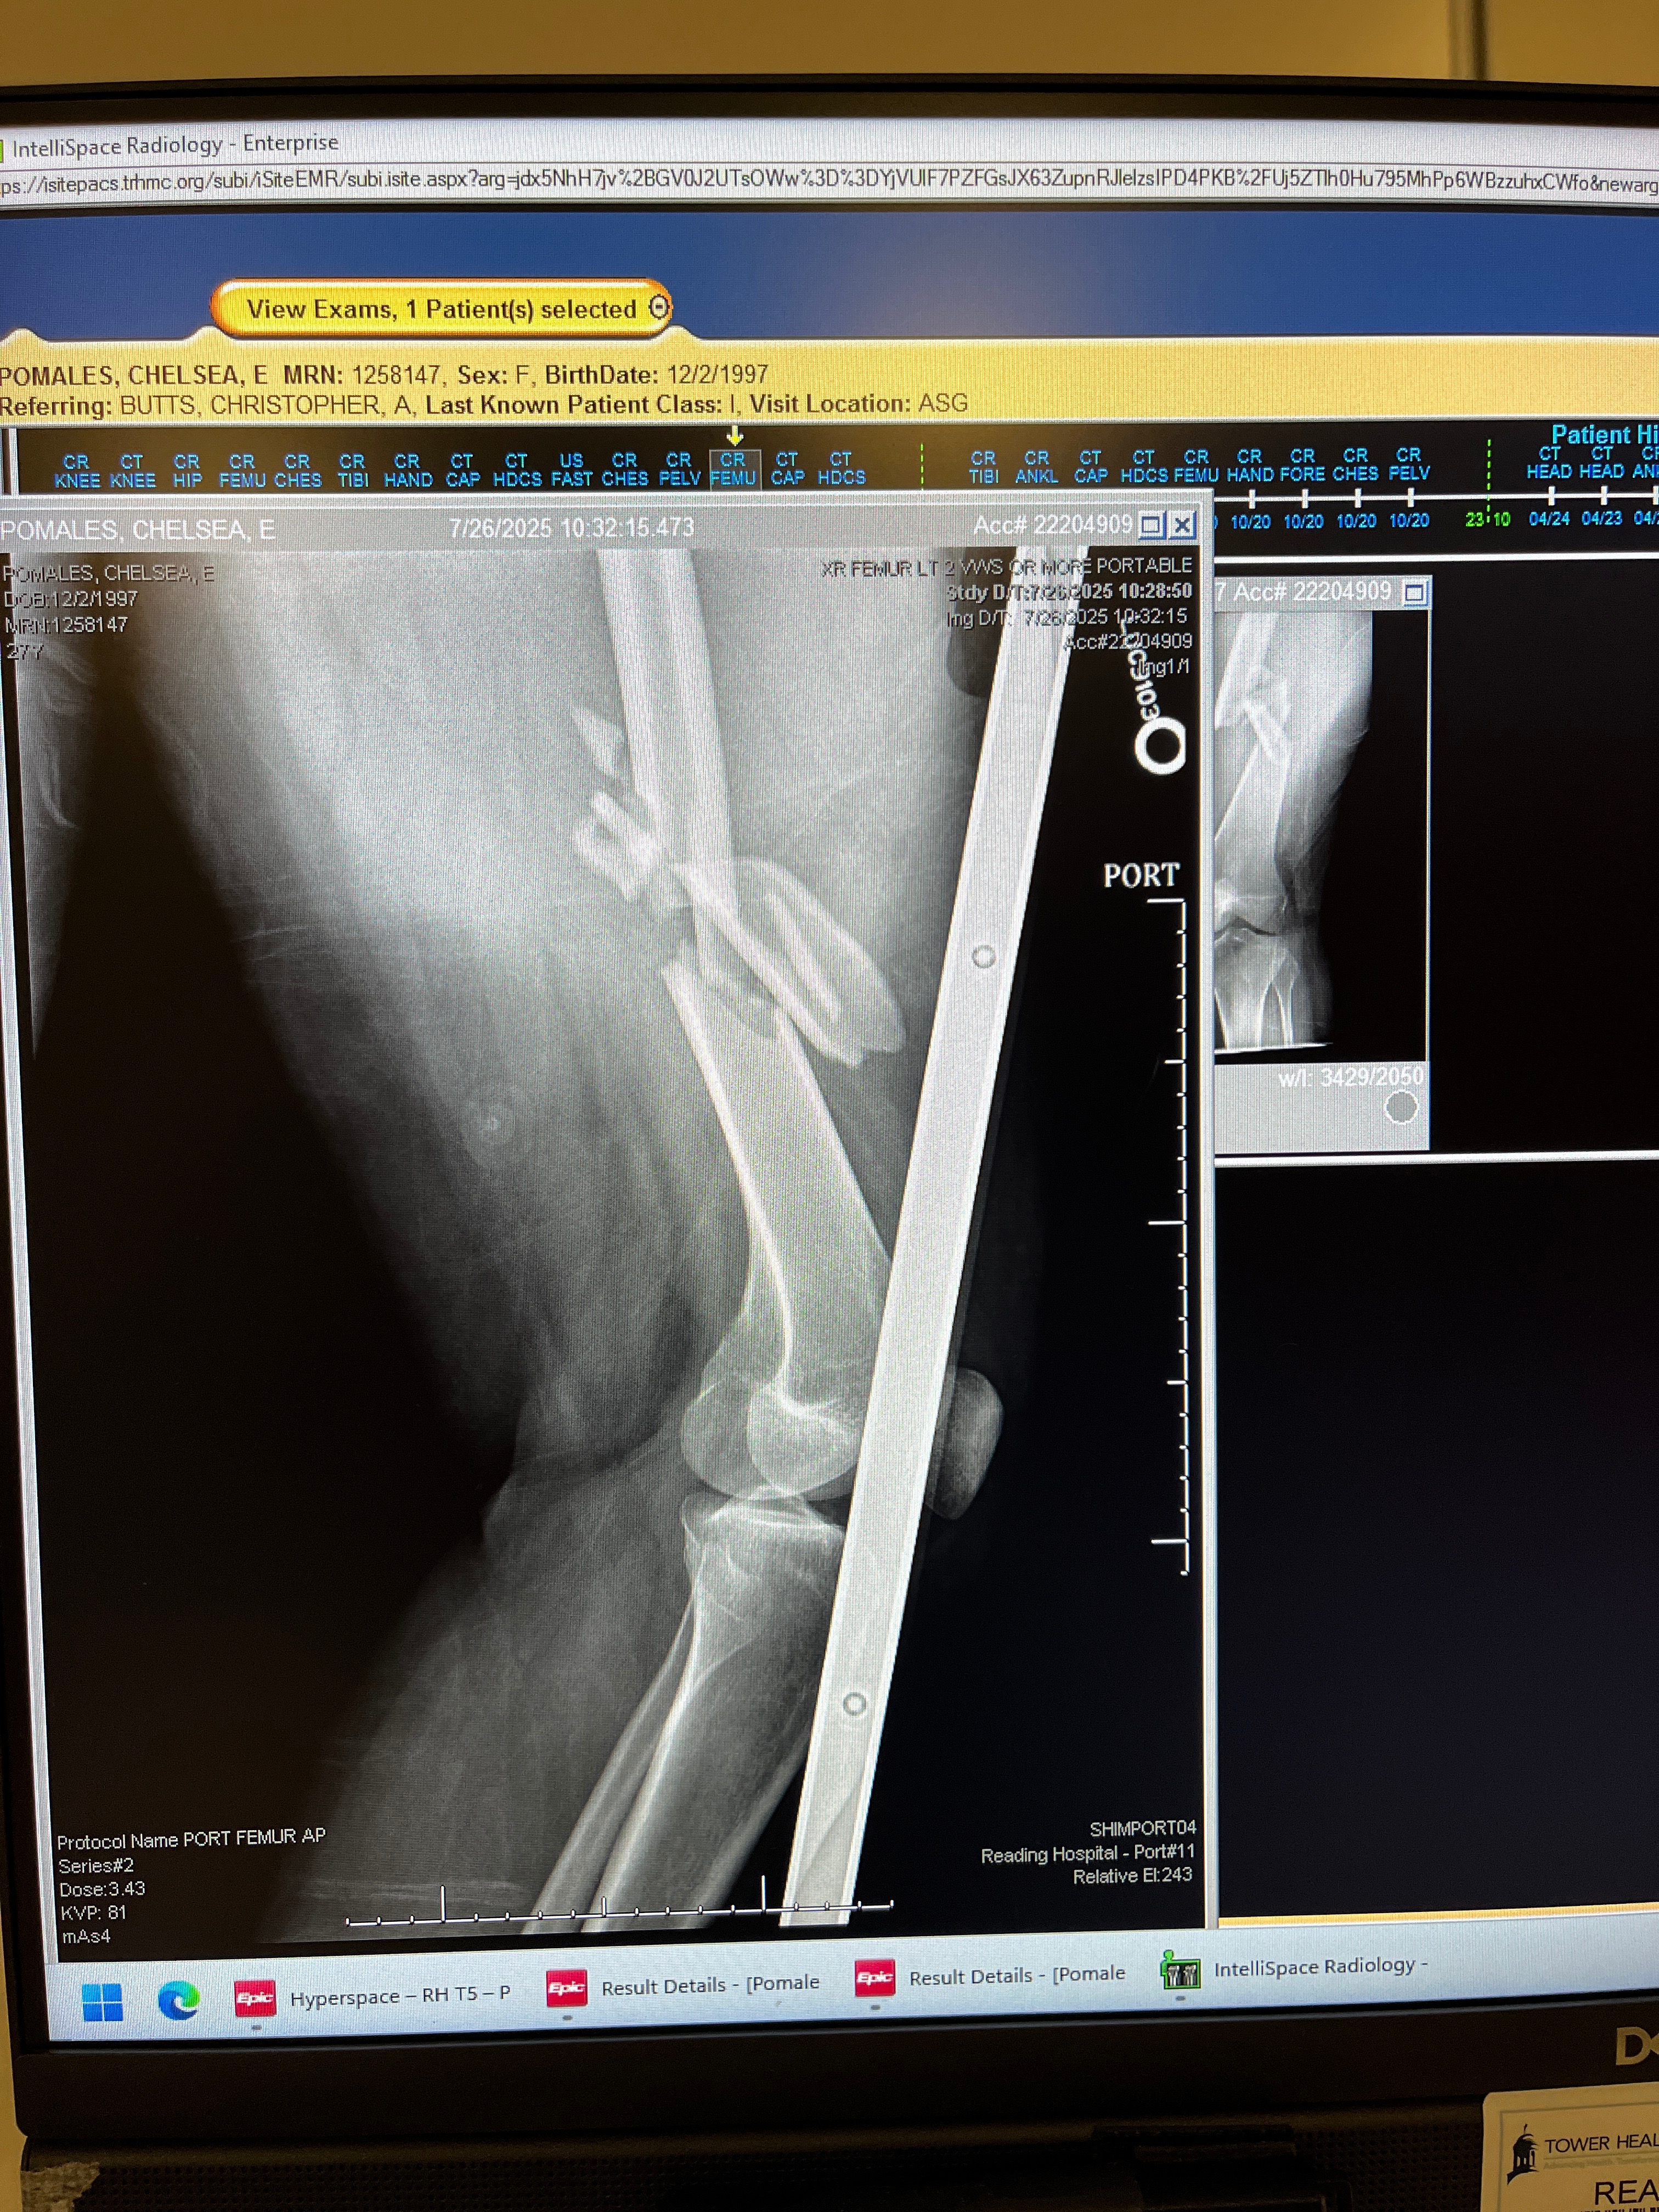

My primary source of transportation has been an electric scooter for the past 5 and a half years. Due to a seizure condition, it’s nearly impossible for me to get my license. I never complained though; my scooter got me and my son wherever we needed to be! On July 26th at 9:30 am, it was a beautiful Saturday morning! I left my friend's house and started heading home, which was only a 5-minute ride. I was driving on the shoulder along traffic when out of nowhere, an Explorer pulled out directly in front of me. There was no avoiding it. The first part of my body that hit the vehicle was my head, which went through the driver's side passenger window, ultimately saving my life since I didn’t have a helmet on. I had gashes in my head and glass in my face. When my body hit the ground, I immediately knew that both my legs were broken. I felt the bones sticking out of my legs. I shattered my left femur and broke my hip. My right leg had a tib-fib plateau break. Both legs have titanium rods, screws, and plates. They say 6 months to a year until I can walk assisted by a walker. I was denied by 7 rehab centers due to the extensive damage to my legs and my non-weight-bearing status. I also broke my left hand. But even with being denied therapy, I literally drag myself off the bed to the bedside toilet and I drag myself on and off my wheelchair. I can’t stand, I can’t walk, but I can’t give up. I have my little guy depending on me.